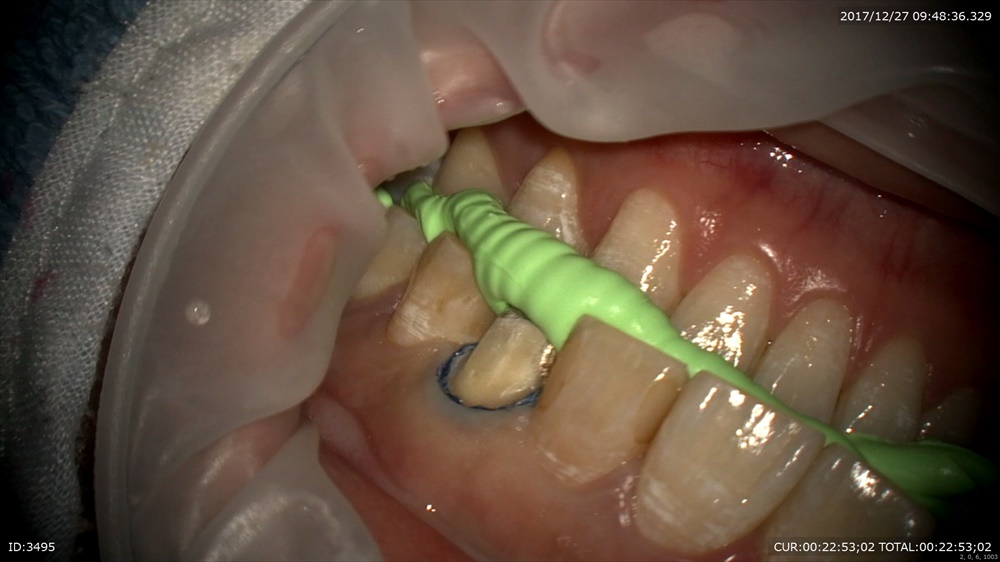

精密な型取り。左上の糸きり歯は大切な歯です。ハイブリットクラウンの型取り。

昨日も書きました。精密さは準備から 糸をまいて

少し研磨。マイクロでミクロで診ていきます。

2本目のコード

かみ合わせ。1本の歯ですが型は全額で。かみ合わせを整える準備です。

型取り

明日からこの方アメリカだそうです。仮歯も丁寧に仕上げました。